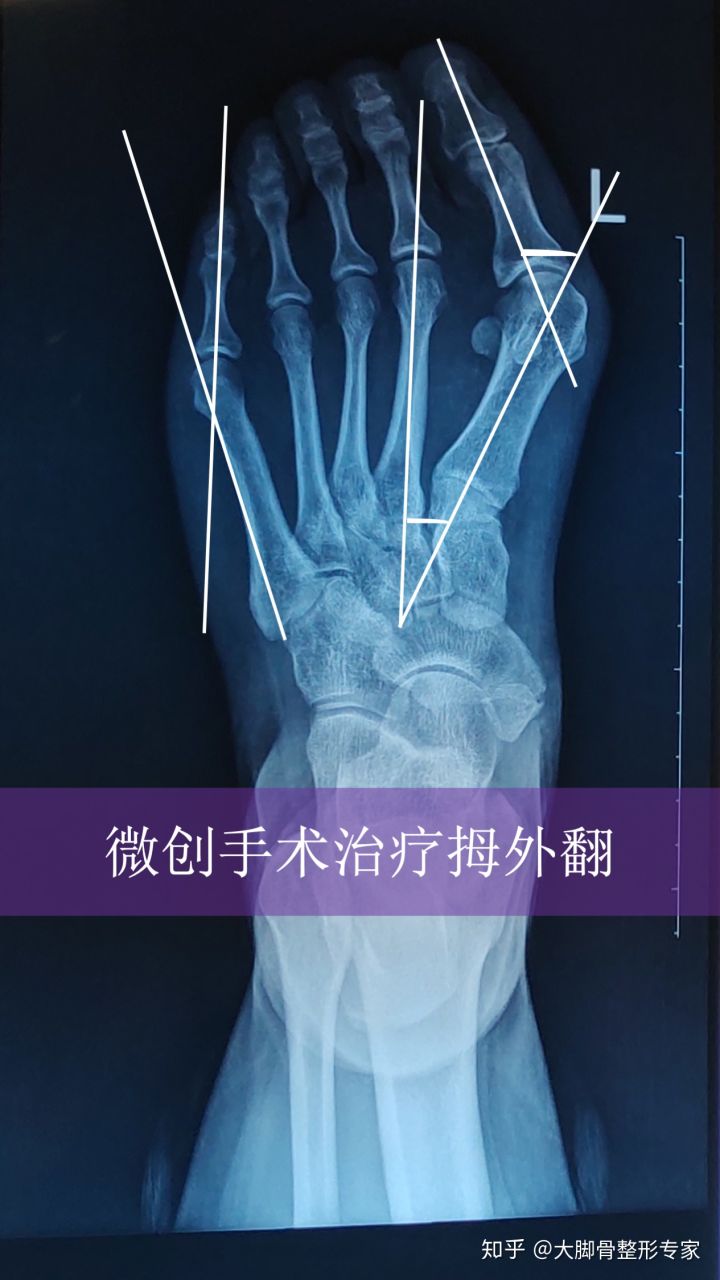

题主小拇趾外侧有个明显的凸起,摸上去硬邦邦的,这个俗称小脚骨,我们看到的外观其实是里面骨头的原因,如下图:

究其原因是里面的第五跖骨向外侧偏斜,与向内侧偏斜的第五趾骨形成犄角,表现出来的就是小脚骨。如下图所示,请看造成局部凸起是因为本该在中轴线上的骨头形成了犄角。

拇外翻是里面的骨头长歪了